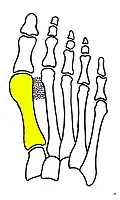

Technique

Syndesmosis procedure addresses specifically the two fundamental problems of metatarsus primus varus deformity that gives rise to the bunion deformity. They are leaning and instability of the first metatarsal bone . Syndesmosis procedure uprights the leaning first metatarsal bone with strong binding sutures between it and the second metatarsal bone (Fig. 2) and then also stabilizes it uniquely by creating a fibrous connecting bridge between these two bones (Fig. 3, 4). First metatarsal bone can be readily realigned because by definition of the metatarsus primus varus deformity its first metatarsal is abnormally loose and mobile.